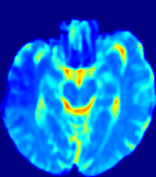

4.3.2 Diffusion Imaging via Advection-Diffusion

Slice #1Slice #2Slice #3Slice #4Slice #5Slice #6Dgtsuperscript𝐷gtD^{\text{gt}}Refer to captionRefer to captionRefer to captionRefer to captionRefer to captionRefer to captionDestsuperscript𝐷estD^{\text{est}}Refer to captionRefer to captionRefer to captionRefer to captionRefer to captionRefer to captionRefer to caption0.300.300.300.240.240.240.180.180.180.120.120.120.060.060.060.000.000.00(mm2/s)𝑚superscript𝑚2𝑠(mm^{2}/s)𝐕est𝟐subscriptnormsuperscript𝐕est2\|\bf{V}^{\text{est}}\|_{2}Refer to captionRefer to captionRefer to captionRefer to captionRefer to captionRefer to captionRefer to caption0.00300.00300.00300.00240.00240.00240.00180.00180.00180.00120.00120.00120.00060.00060.00060.00000.00000.0000(mm/s)𝑚𝑚𝑠(mm/s)

Figure 15: PIANO identifiability testing: diffusion imaging via advection-diffusion. Top row shows Dgtsuperscript𝐷gtD^{\text{gt}} used for simulating ground truth pure diffusion. Rows below show the estimated Destsuperscript𝐷estD^{\text{est}} and 𝐕est2subscriptnormsuperscript𝐕est2\|{\bf{V}}^{\text{est}}\|_{2} on corresponding slices. Note that the plotted value scale for 𝐕est2subscriptnormsuperscript𝐕est2\|{\bf{V}}^{\text{est}}\|_{2} is 0.01 of that for Dgtsuperscript𝐷gtD^{\text{gt}} and Destsuperscript𝐷estD^{\text{est}}.

Similarly, we test the behavior of PIANO when estimating both advection and diffusion from a pure diffusion-driven process. The goal is to determine if PIANO is able to recognize that there is only diffusion governing the given concentration time-series. We use the same ‘Diffusion Imaging’ data simulation of Sec. 4.2.1 as the concentration dataset, PIANO estimates both velocity 𝐕estsuperscript𝐕est{\bf{V}}^{\text{est}} and diffusivity Destsuperscript𝐷estD^{\text{est}}. Estimation results in Fig. 15 confirm PIANO’s identifiability again: the estimated 𝐕est2subscriptnormsuperscript𝐕est2\|{\bf{V}}^{\text{est}}\|_{2} is almost invisible compared to Destsuperscript𝐷estD^{\text{est}}, even plotted with a 1%percent11\% value range compared to that for Destsuperscript𝐷estD^{\text{est}}. On the other hand, Destsuperscript𝐷estD^{\text{est}} achieves comparable estimation performance as ‘Diffusion Imaging via Diffusion’ in which PIANO predicts Destsuperscript𝐷estD^{\text{est}} alone (shown in Fig. 13).